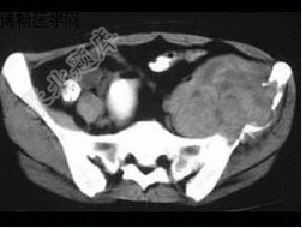

- 单项选择题患者,男性,33岁,近2年来感左髂部疼痛,活动后加重,3周前由于剧烈运动后左下肢活动不能,查体左髋压痛明显皮肤稍显红肿,请结合所提供的图像,选择最佳选项( )

A、骨囊肿

B、软骨瘤

C、骨巨细胞瘤

D、软骨肉瘤

E、动脉瘤样骨囊肿